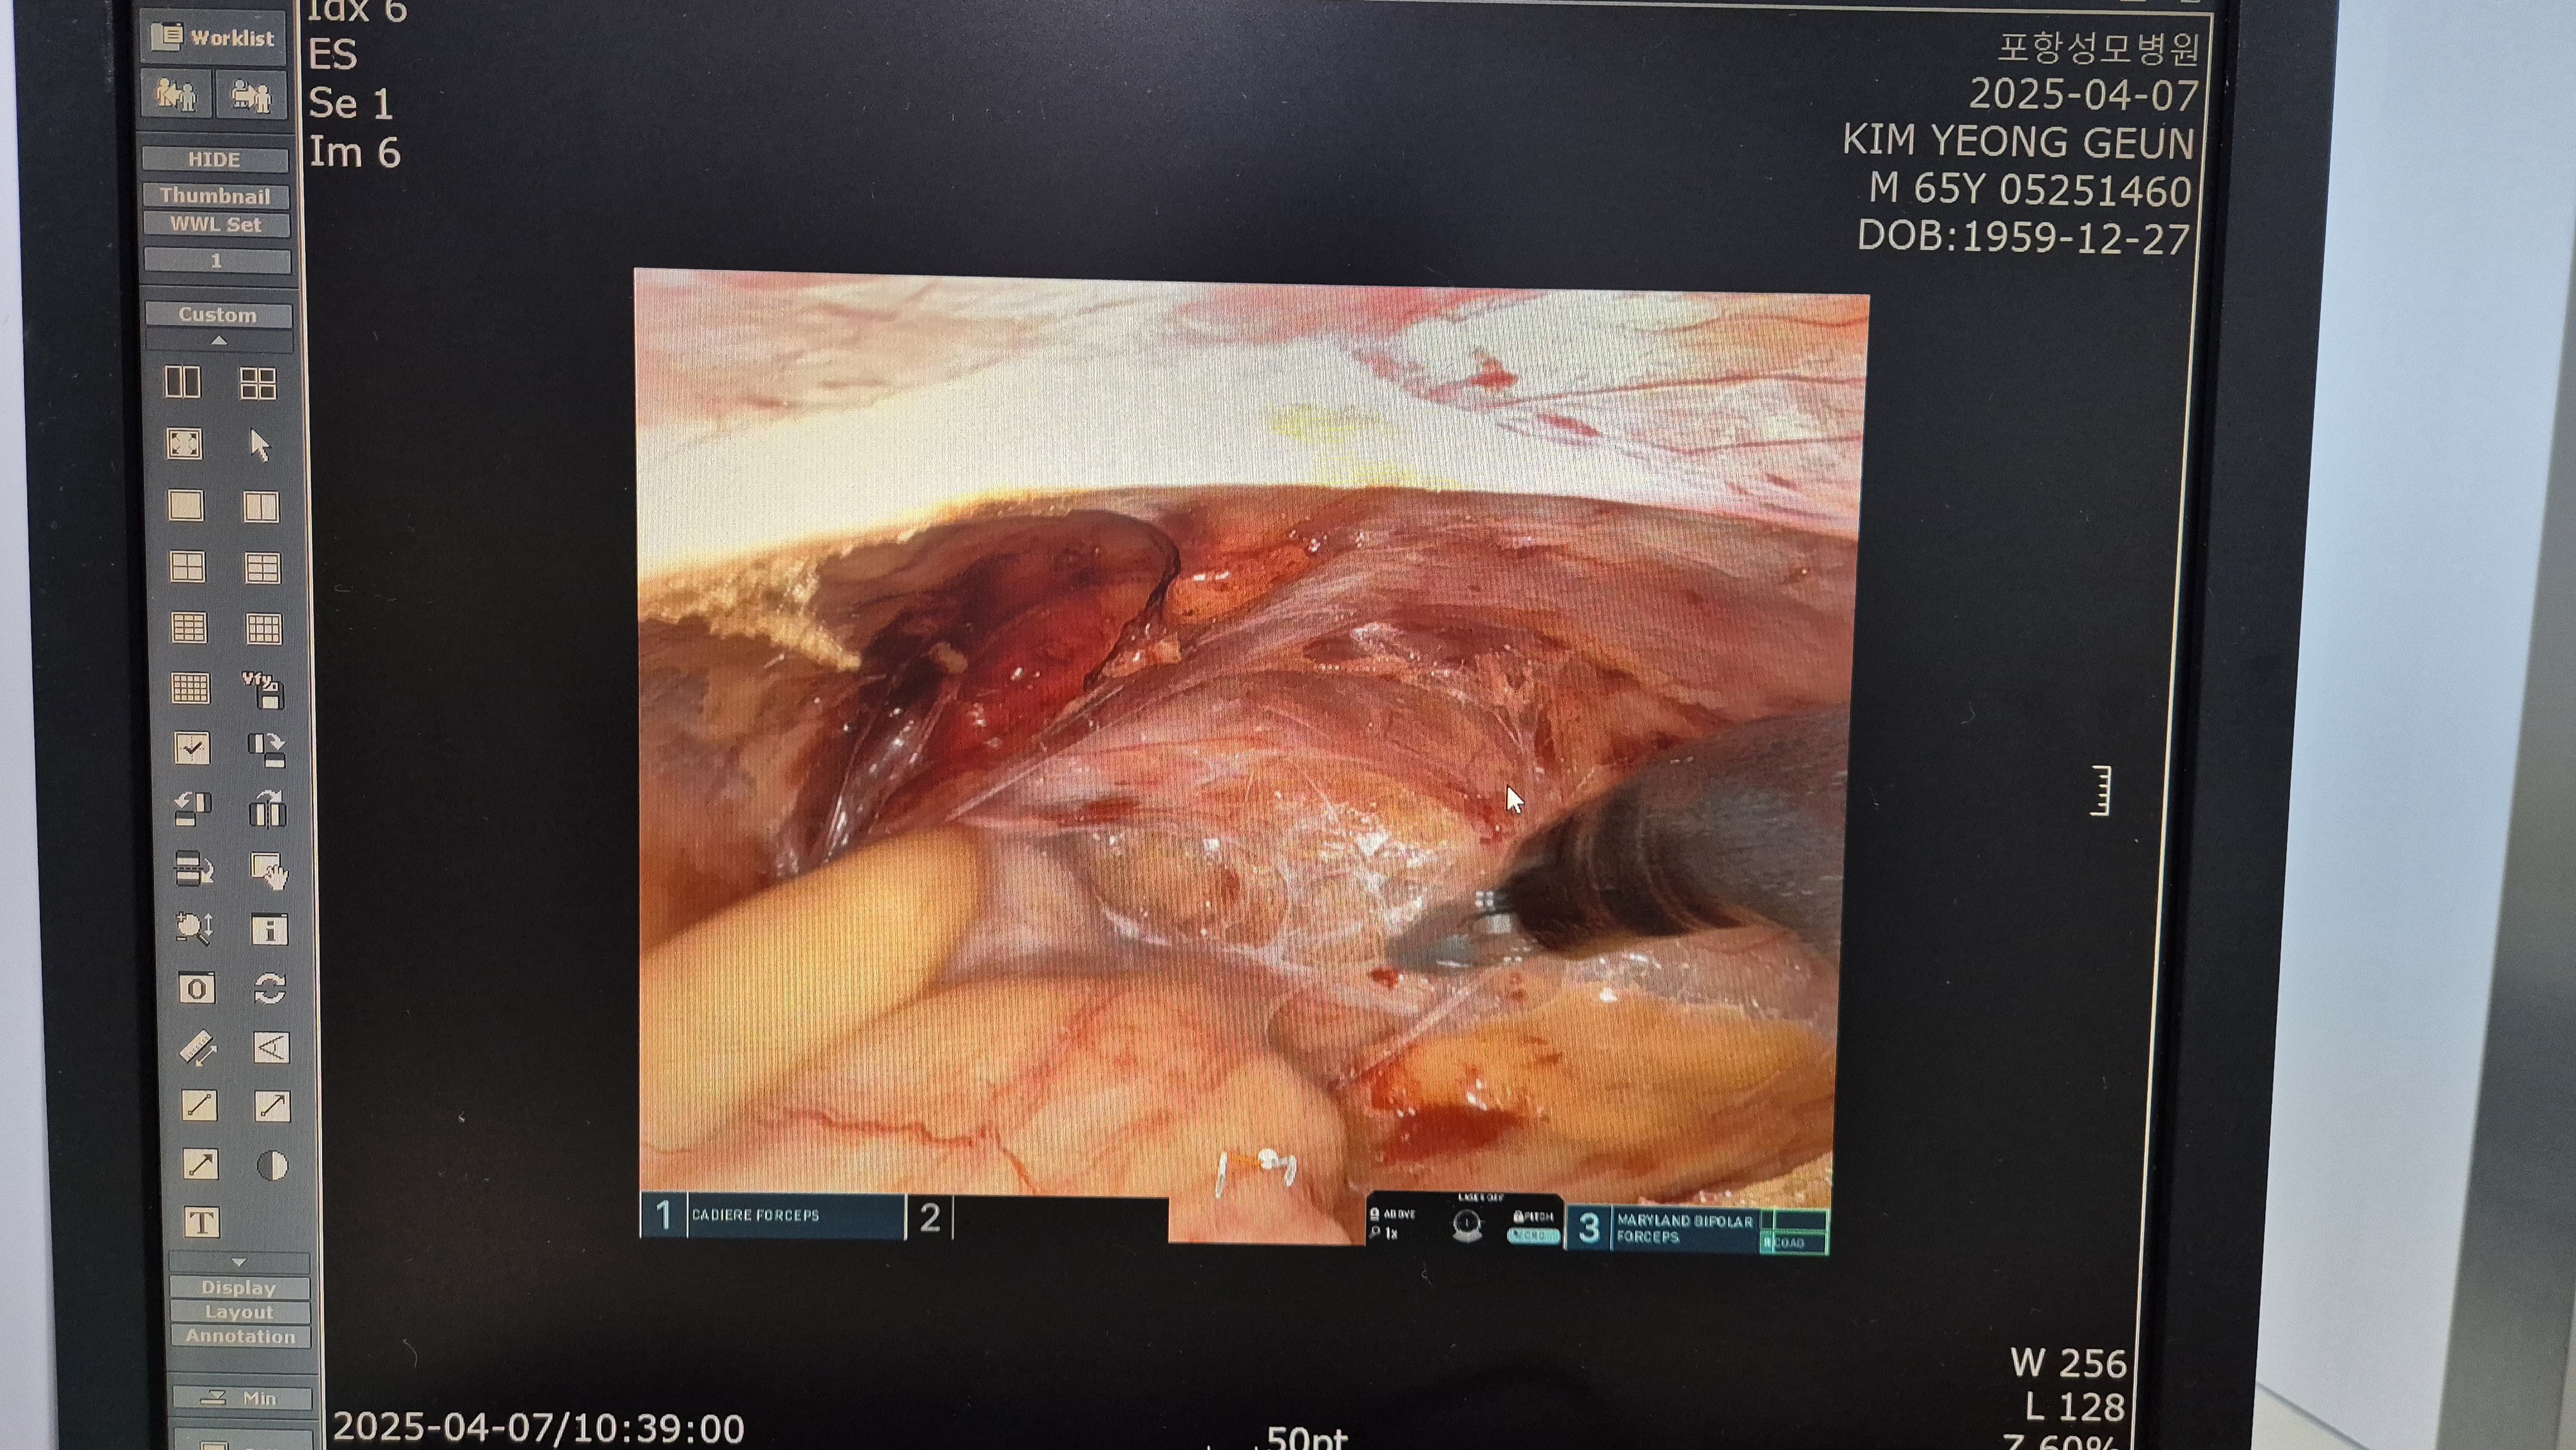

방금 다빈치sp 로봇 탈장교정술을 시행했습니다.

탈장 확인후.

복막을 열고.

탈장낭 박리후 메쉬고정.

복막 봉합.